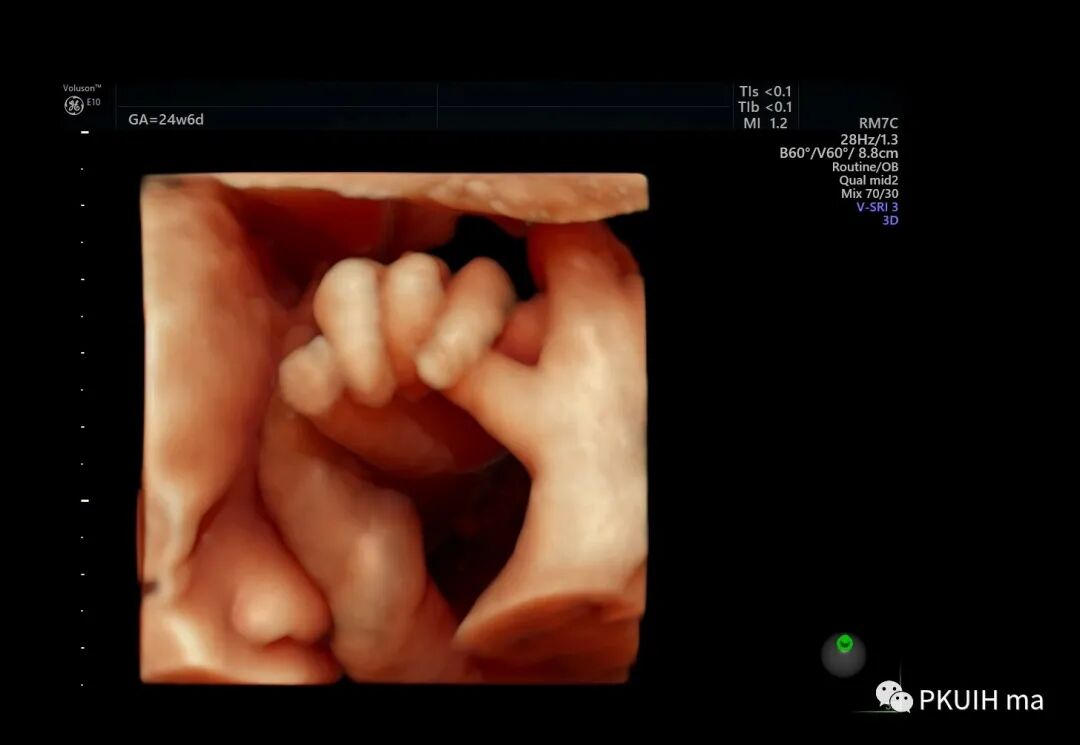

胎儿的小手